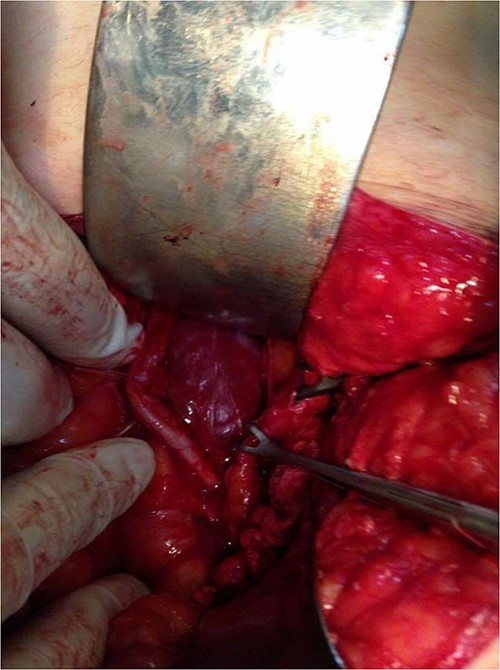

Surgical resection of the tumor was performed using a lower midline incision and a Kocher maneuver was used for the dissection of the retroperitoneum. The mass was found, lying posterior to the left ureter and gonadal vessels (both of them isolated by a rubber tube) and compressing medially on the aorta above the bifurcation. The feeding arteries of the tumor were found to originate from retroperitoneal tissue instead of from the abdominal aorta, and each vessel was ligated before the tumor was removed. There was no evidence intraoperatively of the invasion of the surrounding structures. The mass was well capsulated showing a lobulated surface and dark fleshy color (Figs 4 and 5). The postoperative period was uneventful, and the patient was discharged home on Day 3 after the operation.